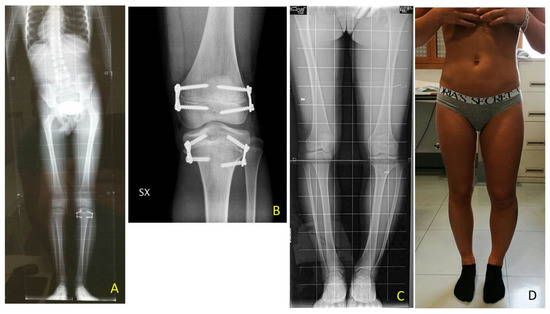

Figure 10. BWS (Beckwith-Wiedemann syndrome) female patient with severe LLD (leg length discrepancy) left. At age of 7 years with a length discrepancy of femur of 1.5 cm and of 3.5 cm of tibia a PTE (temporary proximal tibia epiphysiodesis) was performed: (A) at age of 9.4 years femur discrepancy of 3.0 cm was present leading to a severe pelvis obliquity without shoe lift correction as shown in X-ray od spine and lower extremities; (B) postoperative X-ray in antero-posterior projection showing performed DFE (temporary distal femur epiphysiodesis); (C) at age of 12.7 years, after reaching leg length equality, removal of implants was performed. X-ray showing screw breakage on lateral aspect of tibia; (D) clinical aspect at follow-up with mild varus knee deformity bilaterally and nonpelvic obliquity.

Temporary epiphysiodesis’s main complications were: 14 implant migrations with secondary varus-valgus axial deviation in a total of 6 patients. Hemi-epiphysiodesis was necessary to correct axial deviation that occurred during growth. To have a greater effectiveness in growth plate block, new bigger “quad” plates were used (8) in 6 cases. In only two cases screw breakage occurred during surgical removal (Figure 10).

In 6 patients, a revision of the plate’s configuration was necessary. Due to plate migration the eight plates were re-implanted. When axial deviation occurred, hemiepiphysiodesis was performed. In the first follow-up, after the first surgical procedure, 4 varus axial deviations and 1 plate migration occurred. After the second procedure, 3 valgus and 1 varus axial deviations, 1 plate migration, and 2 screw breakages occurred.

All the tibial and femoral plates were removed in 11 patients after LLD final correction: 10 patients underwent 3 surgical procedures, one a total of 7 procedures; 8 patients had no complications; 6 patients had axial deviation and 2 patients screw breakage.